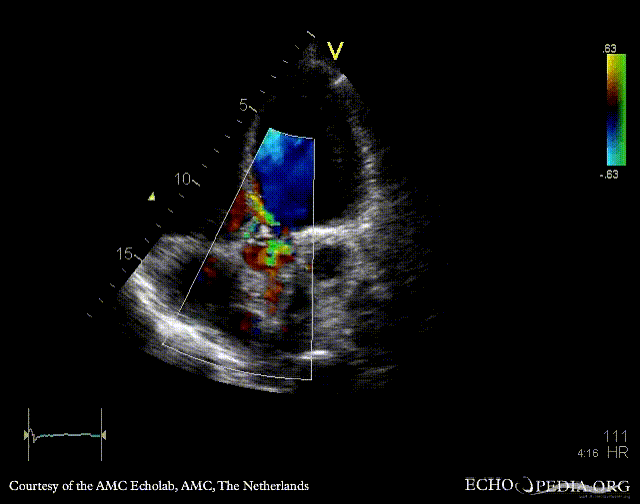

PLAX with Color Doppler: severe aortic regurgitation A4CH: dilated atria and ventricles, poor function of left ventricle